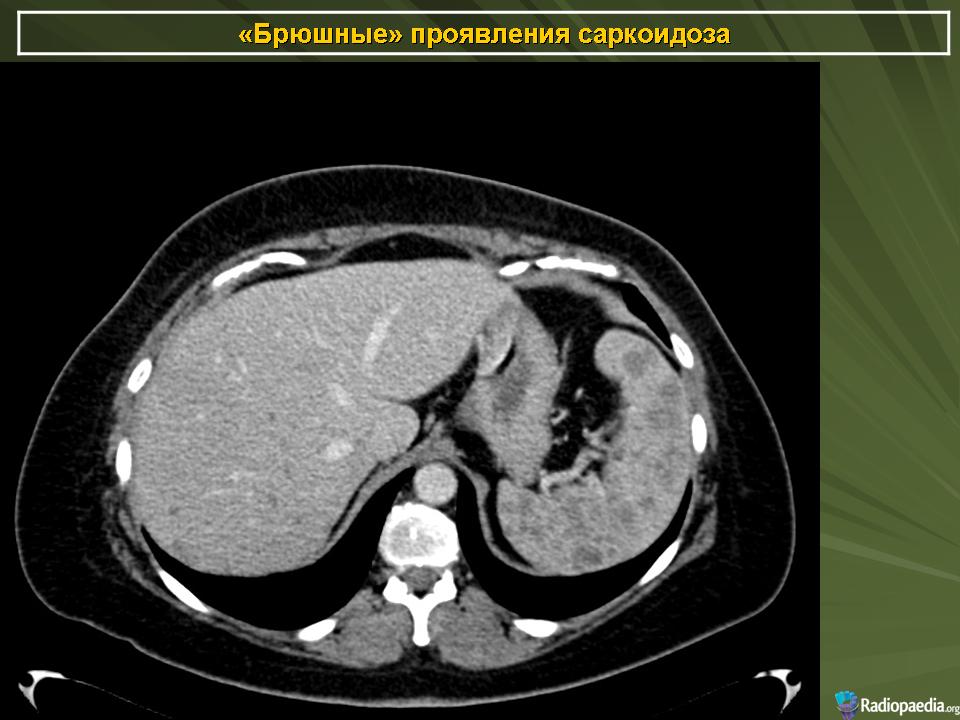

Саркоидоз 3. Брюшной саркоидоз. +

По мнению греческих рентгенологов очаговые изменения в селезёнке и печени являются необычными проявлениями абдоминального саркоидоза. Они описали случай саркоидоза, когда имелись множественные очаговые изменения пониженной плотности в печени и селезёнки на РКТ органов брюшной полости при нормальной рентгенограмме органов грудной клетки. Диагноз был подтверждён биопсией печени (Thanos L. et al., 2002).